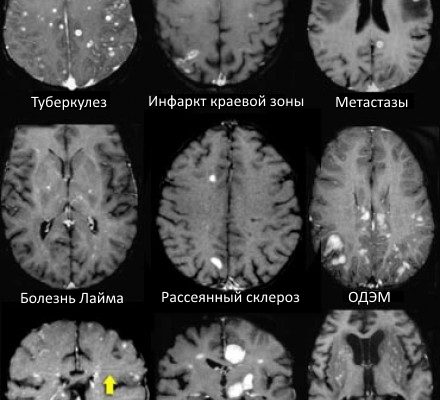

изменений базальных ганглиях

Исследования изменений в базальных ганглиях: что мы узнали о роли этого мозга? Базальные ганглии – одна из ключевых структур головного мозга, отвечающая